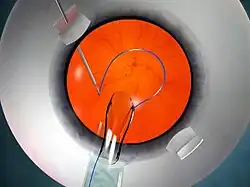

Fig 3: Animation showing glued IOL surgery. Note the flaps made on the white portion of the eye (sclera). The IOL is injected inside the eye and one end (haptic) is grasped with the glued IOL forceps

The glued IOL technique consists of making two partial-thickness, approximately 2.5 mm by 2.5 mm, scleral flaps exactly 180° apart, followed by a sclerotomy with a 20-gauge needle 1 mm from the limbus. A 23-gauge vitrectomy cutter is introduced from the sclerotomy site, and a thorough vitrectomy is done to remove all the vitreous tractions. A corneal tunnel is fashioned, then a 23-gauge glued-IOL forceps is passed through the sclerotomy site, and the tip of the leading haptic of the IOL is grasped, which is then externalized and brought out onto the ocular surface (Fig 3). Similarly the trailing haptic is then externalized using the "handshake technique". Scleral pockets are made at the edge of the flap with a 26-gauge needle just parallel to the sclerotomy site, into which the two haptics are then tucked for additional stability (Fig 4). The scleral flaps are then glued back into place using biological glue. The IOLs that can be used are the three-piece foldable IOLs with slightly firm haptics, or a three-piece non-foldable IOL. The glue is then used to seal the conjunctival closure.